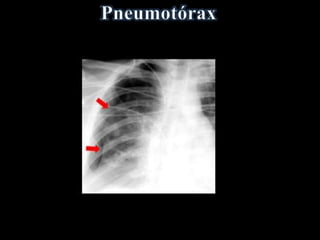

• Ar livre na cavidade pleural

• Faixa de ar (hiperlúcida) entre a pleura

visceral e:

a parede torácica e/ou diafragma

• Desvio de mediastino contralateralmente

• Acentuado na Expiração Forçada